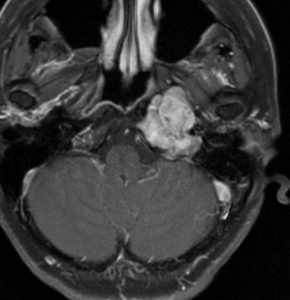

典型的な例1

舌萎縮(舌が右側に曲がっている)に気づいて発見された舌下神経鞘腫です。

舌の右側だけが痩せて萎縮しています,前に出すと麻痺側に曲がります。

舌に波のようなシワができます。

頭蓋底の舌下神経管から頭蓋底部,深頸部に伸びた6cmくらいある大きな舌下神経鞘腫です。舌萎縮以外の症状がないので,手術しないで何年も経過観察していますが大きさは変わりません。右側の画像では内頸動脈が圧迫されていますが,狭窄して血流が悪くなるようなことはありません。